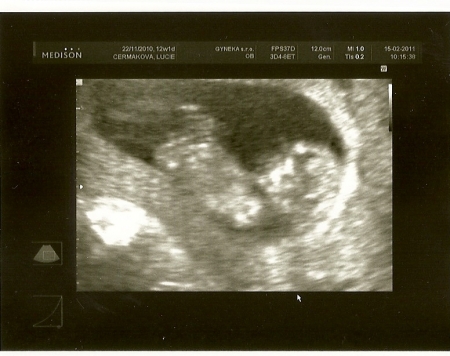

Délka plodu od temene k zadečku je asi 4 cm, váha kolem 8g.

Trojrozměrné znázornění plodu starého asi 10-11 týdnů. I když je mozková část hlavy ještě poměrně velká, rýsuje se pod vypouklým čelem jemný obličej s vyvýšeným nosíkem a malými ústy. V oblasti zad je dobře patrná páteř složená z jednotlivých obratlů. Šipkami shora dolů označeny: temeno, pupečník, levá paže, kostrč.